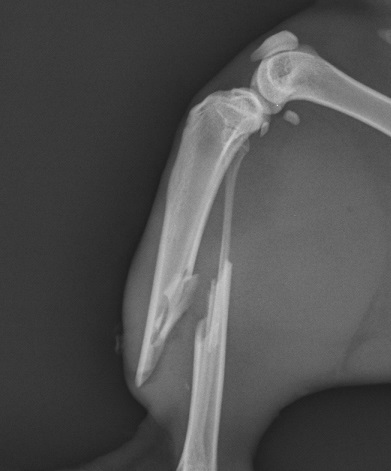

AO/ASIF internal fixation system is a cost effective method of fracture repair that has stood the test of time, and is adaptable to many fractures. We offer sizes from 1.5mm to 4.5mm and on occasion use a range of plates from veterinary cuttable plates to Limited Contact Dynamic Compression plates and hybrid plates.

We also offer Minimally Invasive Plate Osteosynthesis (MIPO) solutions to certain qualifying fractures and combination solutions for non-load sharing fractures.